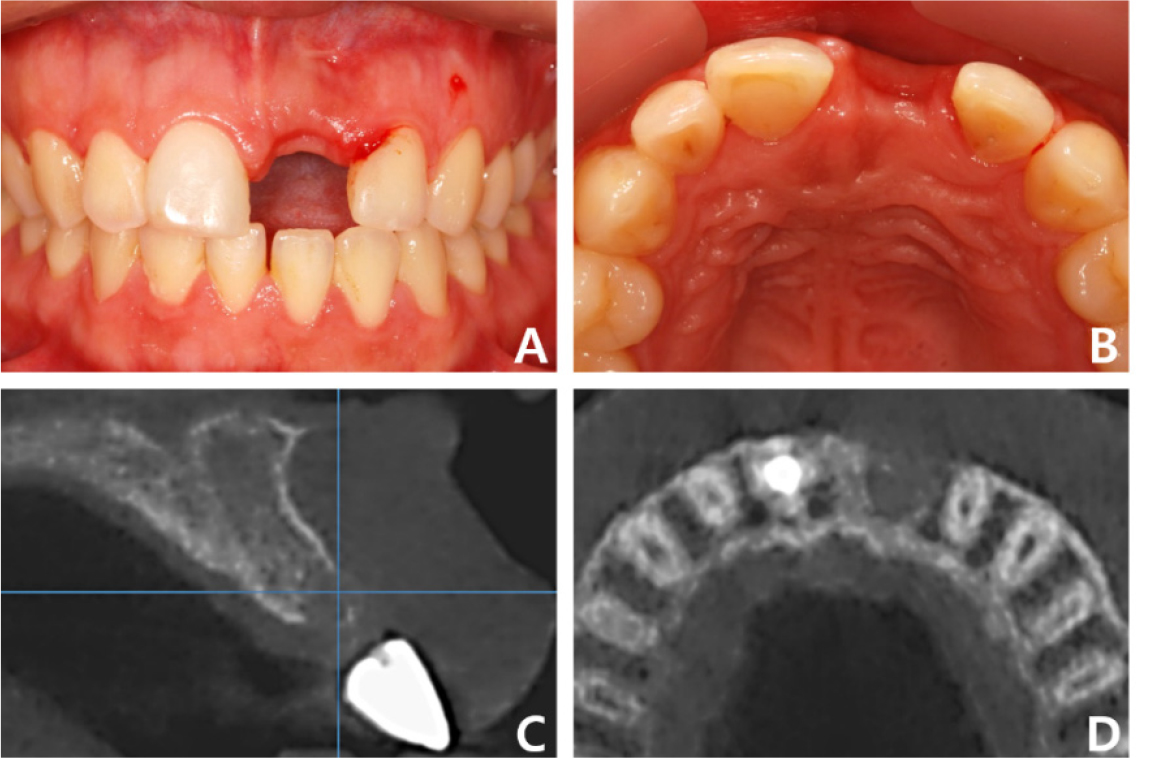

The alveolar bone bed was evaluated for implant placement after removal of the old prostheses. In particular, the left side of the anterior maxillary ridge was severely atrophic due to the long-term edentulous state after tooth extraction. CT showed sufficient bone height; however, the bone width was approximately 3 mm, indicating a narrow and thin alveolar ridge. Because the patient was old, bone graft using allogeneic, rather than autogenous, block-bone was considered to minimize damage. An incision was made in the left maxillary surgical site under local anesthesia. After a full thickness of periodontal flap was elevated, an allogeneic block-bone (Tricortical Block 20×40 mm; Hansol Medical) was adjusted into a ‘J’ shape and fixed to the alveolar bone using two micro screws (Fig. 6). The cancellous surface of the block-bone was attached to the alveolar bone and the cortical surface to the soft tissue. Additionally, a particulate bovine bone graft (Bio-Oss®; Geistlich Biomaterials) was placed around the grafted block-bone using a collagen membrane (Bio-Gide®; Geistlich Biomaterials), and the wound was sutured without tension. Six months after grafting, two implants with length 10.0 mm and diameter 4.0 and 4.5 mm (IU; Warantec) were placed in the #23 and #25 regions, respectively (Fig. 7).

Fig. 7.

Case 2: Intraoral and radiographic views of grafted site. (A) Sufficient bone bed for implantation is observed after block-bone grafting, (B) Two implants have been placed and submerged at the grafted site, (C) Sagittal CBCT image of the grafted site before implantation, (D) Sagittal CBCT image of the grafted site after implantation. CBCT, cone-beam computed tomography.

After a sufficient remodeling period of six months, the surgical site was evaluated as stable, and healing abutments were connected. The final 4-unit implant-supported FPD with a mesial cantilever was installed after the provisional phase (Fig. 8A, 8B). All procedures regarding implantation of allogeneic block-bone grafts were successfully performed, and no surgical-site complications were observed on CT three years postoperatively (Fig. 8C). The patient was satisfied with the aesthetic and functional outcomes of full-mouth rehabilitation using implant-supported FPDs.